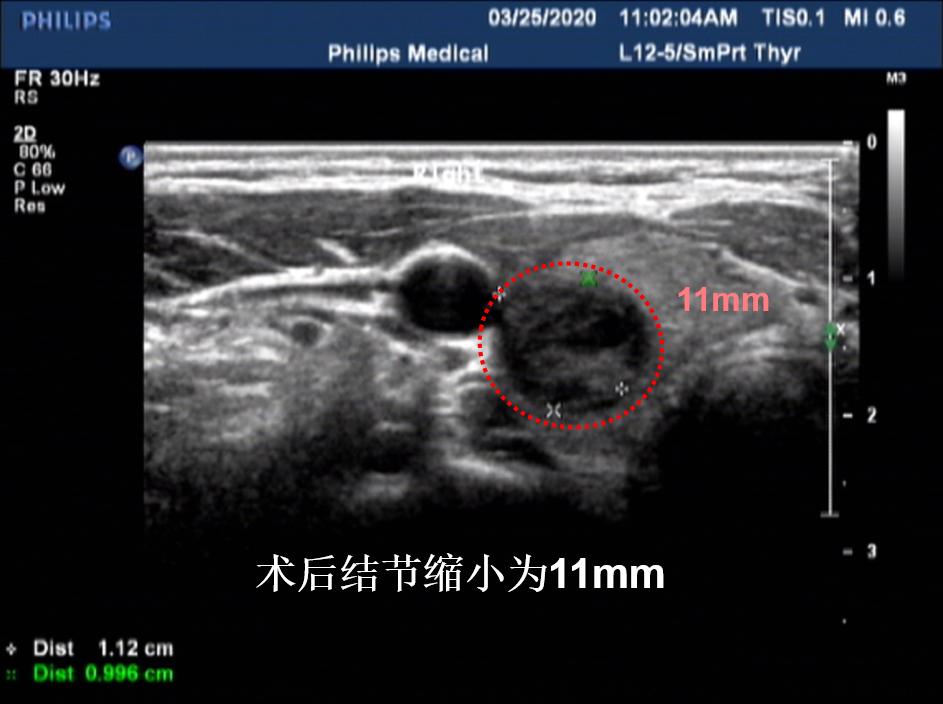

病例③: 25mm的甲状腺结节微创消融后1年半,完全吸收

微创消融前后超声对比,结节完全消失